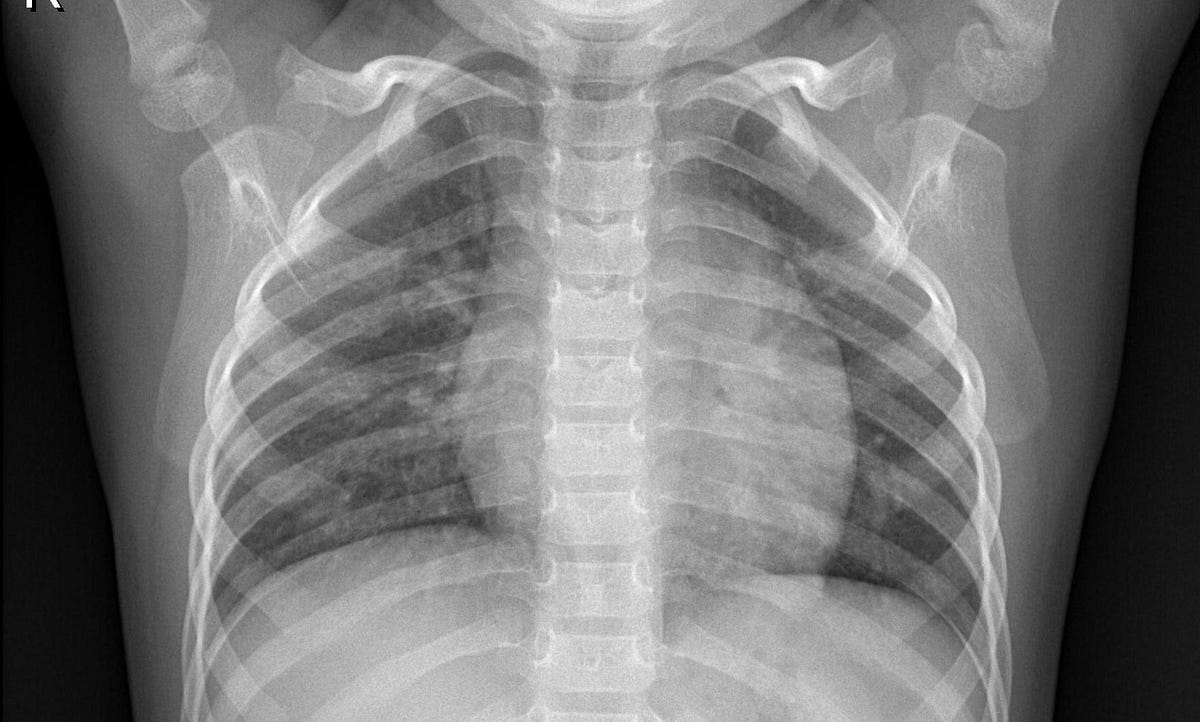

Chest X Ray Chest Radiography Nurse Study Guide Nursing Study Guide Radiography Nursing Study